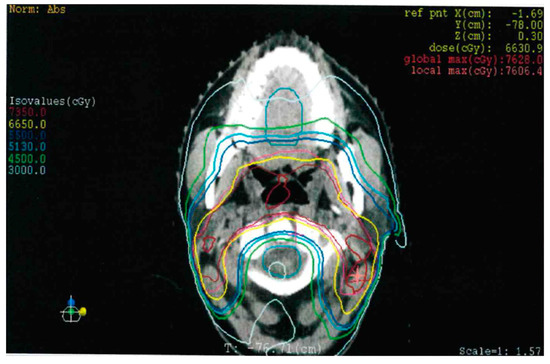

2. Detailed Case Description